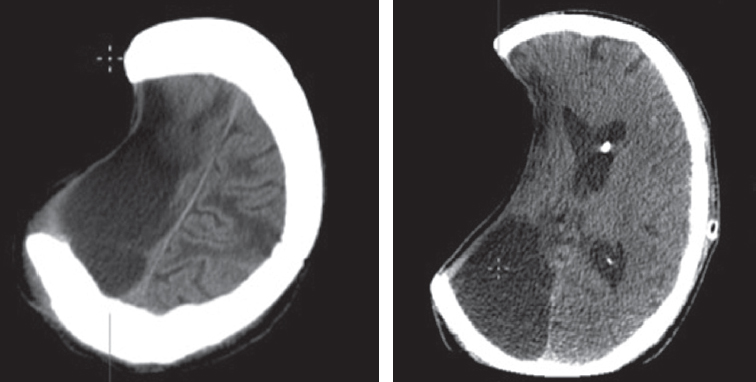

Fig. 5. Patient S. CT — trepanation defect in the frontal-temporal-parietal region on the right, measuring 9.2 × 13.7 cm (defect area 153 cm2). A zone of cystic-atrophic changes in the right hemisphere is determined. The median structures are shifted to the left by up to 0.4 cm. The lateral ventricles are dilated and symmetrical. In the area of the body of the left lateral ventricle, there is a proximal edge of the ventricular shunt (history of mine-blast injury)

Рис. 5. Пациент С. КТ — трепанационный дефект в лобно-височно-теменной области справа размерами 9,2 × 13,7 см (площадь дефекта 153 см2). Определяется зона кистозно-атрофических изменений правой гемисферы. Срединные структуры смещены влево до 0,4 см. Боковые желудочки расширены, симметричны. В области тела левого бокового желудочка имеется проксимальный край вентрикулярного шунта (в анамнезе минно-взрывная травма)

Fig. 6. Patient G. No active complaints consistent with brain injury, conscious, no neurological symptoms. Upon examination, the entrance holes of a penetrating blind craniocerebral wound are visualized in the left temporal region (at the time of injury, consciousness was not lost). CT of the head — a hypodense wound channel with the presence of foreign bodies of bone density was detected in the left frontal region, the wound channel goes upwards into the right frontal region of the brain with the presence of a foreign body of metallic density

Рис. 6. Пациент Г. Без активных жалоб, соответствующих травме мозга, в ясном сознании, без неврологической симптоматики. При осмотре в левой височной области визуализируются входные отверстия проникающего слепого черепно-мозгового ранения (в момент получения травмы сознание не терял). КТ головы — в левой лобной области выявлен гиподенсный раневой канал с наличием инородных тел костной плотности, раневой канал идет вверх в правую лобную область мозга с наличием инородного тела металлической плотности